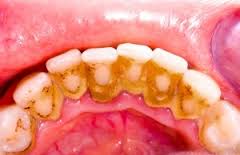

Νεκρά μικρόβια και συστατικά από το σάλιο, αναμειγνύονται με τη μικροβιακή πλάκα και

σχηματίζουν την τρυγία ή κοινώς γνωστή ως ‘’πέτρα’’. Η επιφάνεια της τρυγίας είναι αδρή,

ευνοώντας την προσκόλληση μικροβίων και καθιστώντας δύσκολη έως και αδύνατη την

απομάκρυνση τους. Έτσι στα σημεία με τρυγία είναι πολύ δύσκολη η στοματική υγιεινή,

γι’ αυτό και συνίσταται ο καθιερωμένος έλεγχος από τον οδοντίατρο και ο καθαρισμός.